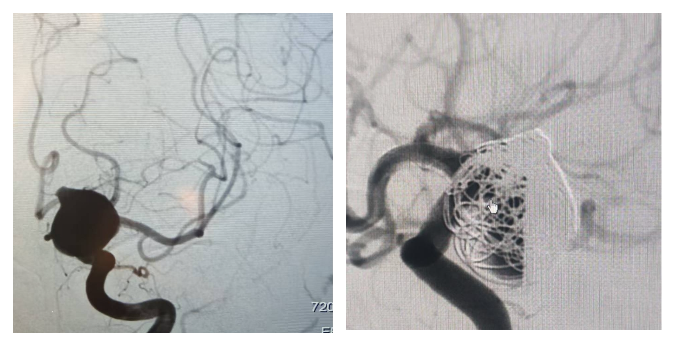

患者武女士因"剧烈头痛2天"来院就诊,经头颅CT检查发现颅内巨大动脉瘤伴蛛网膜下腔出血,随即被收入五疗脑病科。进一步的全脑血管造影(DSA)检查显示,患者左侧颈内动脉C7段(交通段)存在一个尺寸约21mm×20mm的巨大动脉瘤,形态不规则,血流动力学复杂,随时有破裂大出血的风险,致死致残率极高。

手术由北京宣武医院李静伟主任医师主刀,我院五疗脑病科玉山主任医师等专家密切配合。术中,医疗团队克服了血管路径迂曲、动脉瘤形态复杂、支架精准释放等多重考验,成功将Tubridge® Plus血流导向密网支架系统输送至病灶区域。支架精准释放后,在动脉瘤颈口形成了一道有效的"屏障",随后团队通过微导管将弹簧圈致密填入动脉瘤囊内,完成栓塞。

术后造影显示,支架打开充分,与血管壁贴壁性极佳,弹簧圈填塞稳定,形态完美。该项手术的成功实施,充分体现了我院在脑血管疾病诊疗方面的技术实力,也展现了京蒙医疗协作的显著成效。